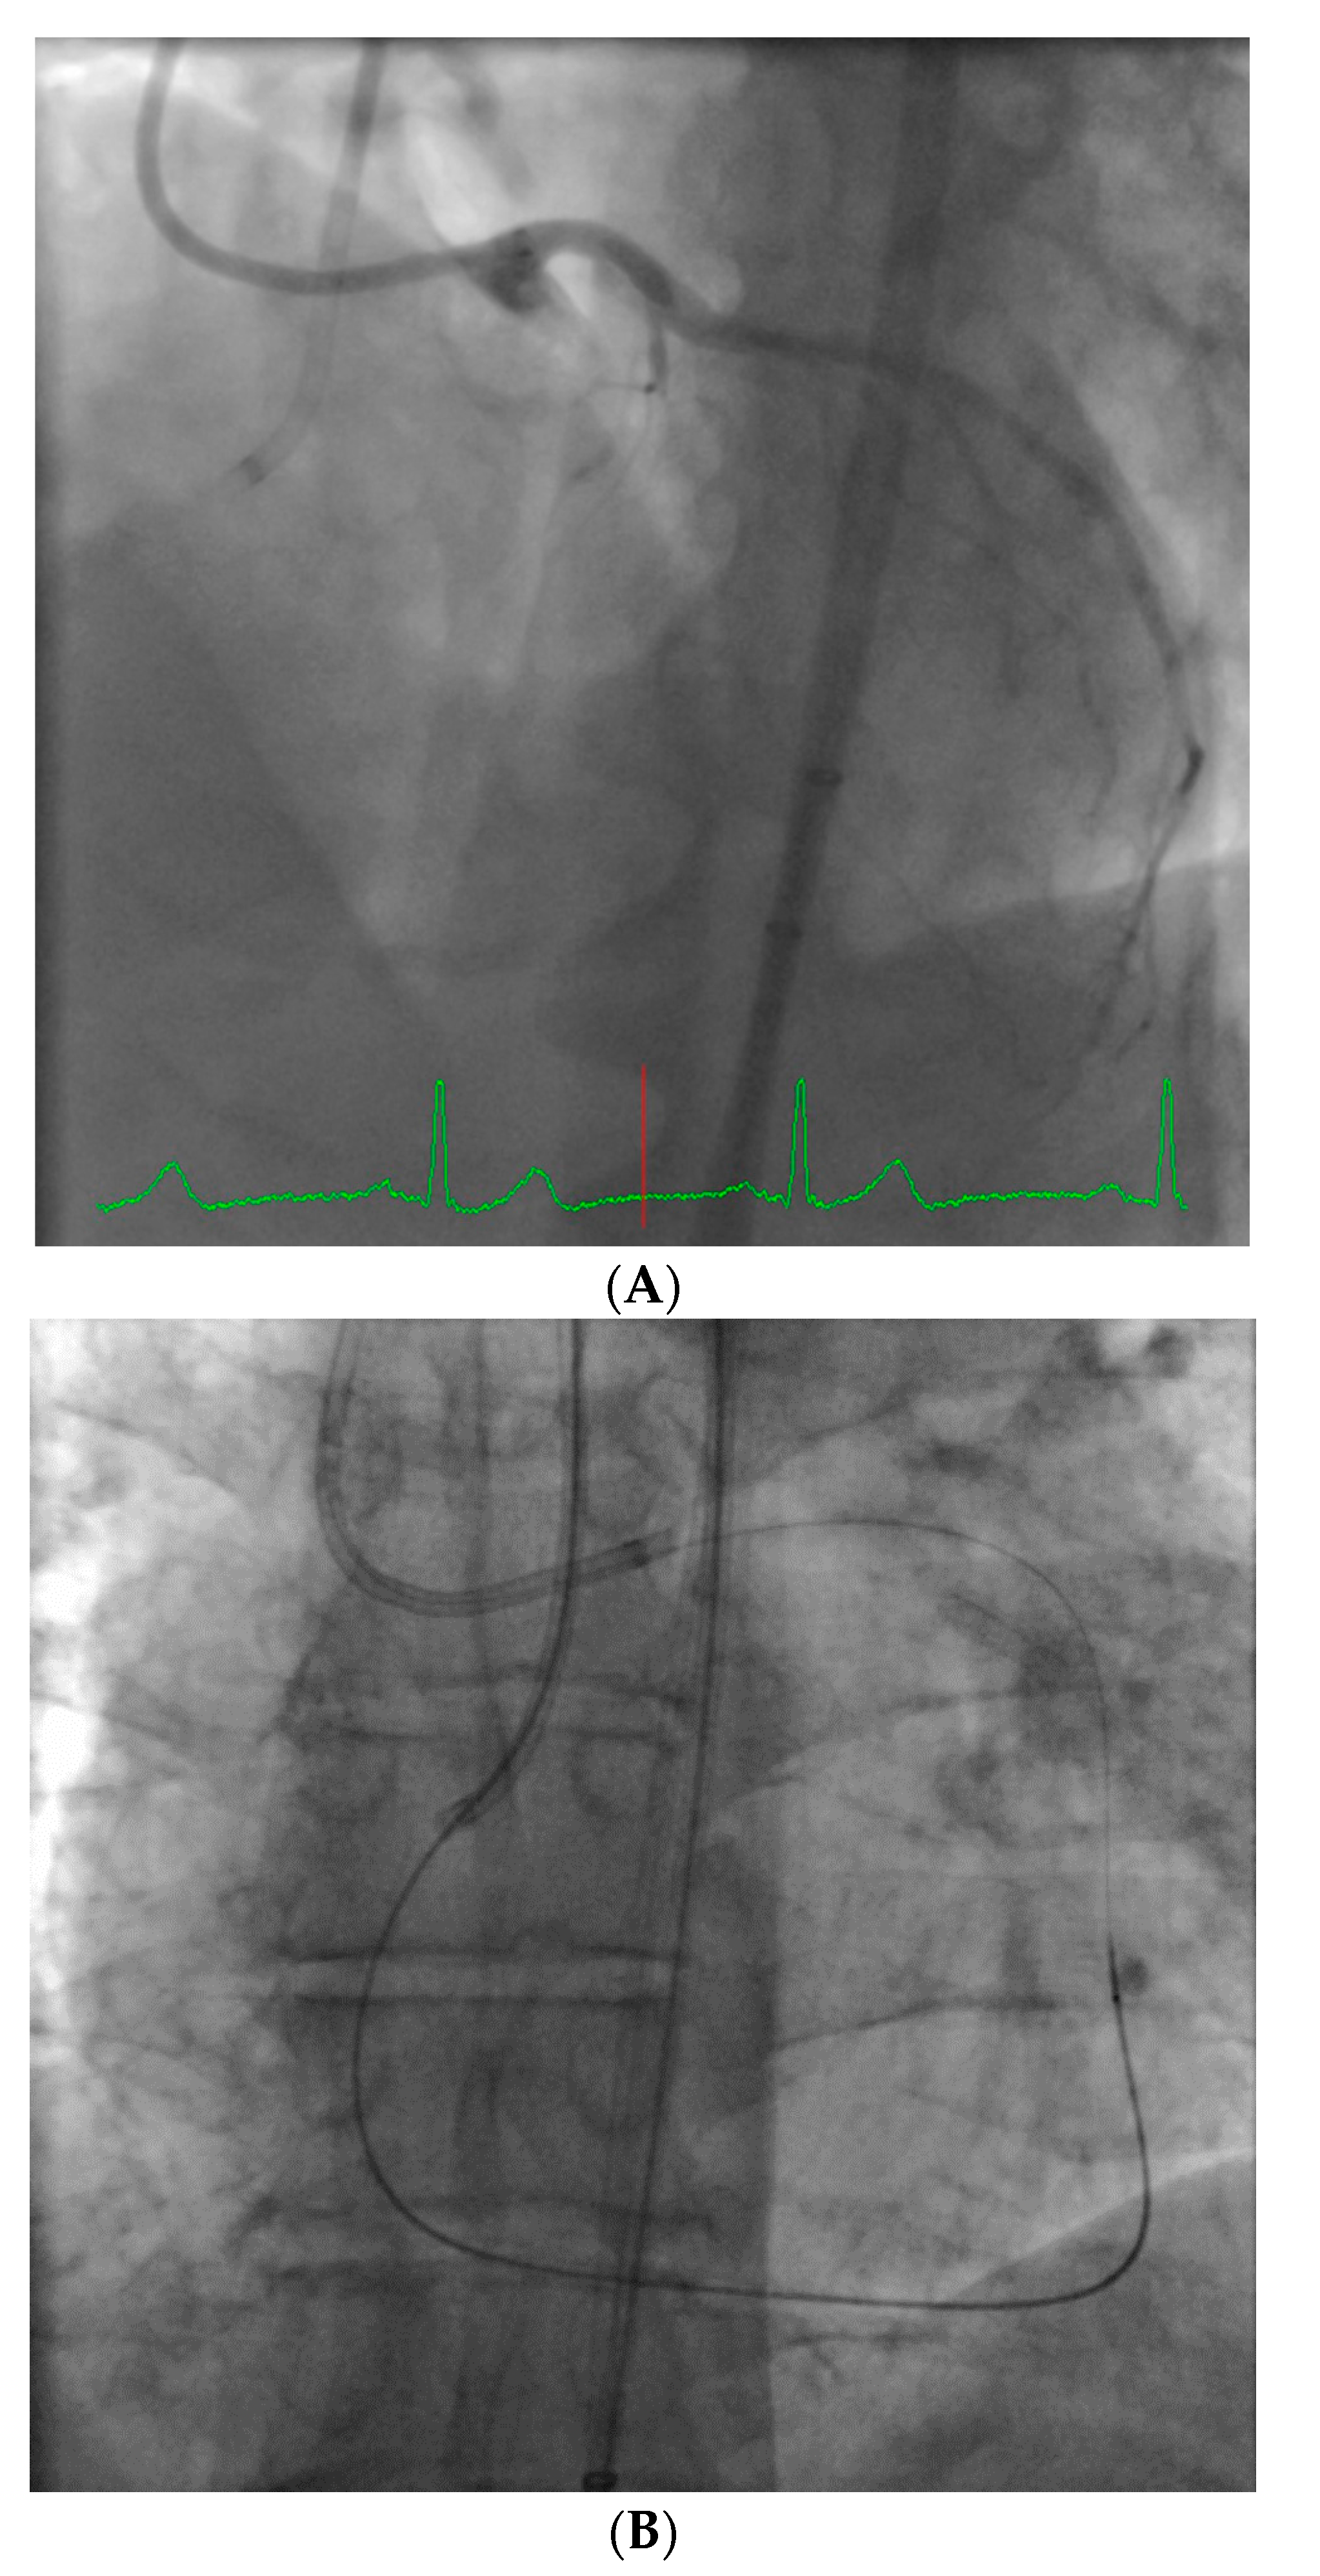

From a pure anatomical standpoint, bifurcation cases with planned kissing stents or kissing balloon angioplasty are not ideal for robotic PCI primarily because the system can only advance one catheter actively. However, bifurcations where provisional side-branch intervention is planned are reasonable choices for robotic PCI. Cases with excessive vessel tortuosity may be successfully performed robotically (Figure 3); however, extreme arterial angulation, or lesions that are severely eccentric or have dissected plaque morphology may require the use of tactile feedback that is not afforded by the robot and are not ideal (Figure 4). Although the advanced wire techniques required for anterograde wire escalation, dissection re-entry approaches, or retrograde approaches in chronic total occlusion intervention are not applicable robotically, we have used the robot to deliver and perform balloon angioplasty, stenting, and post-dilatation after first successfully manually crossing chronic total occlusions with a guidewire (Figure 5). Although the current generation system allows the operator to make fine adjustments in the guide catheter position, ostial lesions, particularly involving the RCA can be very challenging to perform robotically (Figure 6). Finally, cases that require the use of aspiration, atherectomy, filter wires, or certain imaging catheters (OCT and some IVUS), are not suitable for stand-alone robotic PCI.

However, it is worth noting that robotic PCI should not be considered ‘all or none’. Rather than defining what percent of cases are “robot cases”, we think it is more appropriate to consider the question: “What portion of any specific intervention can be done robotically?” Particularly in long and complex cases, if a significant amount of the procedure can be done robotically, it is worthwhile to include the robot in the case in order to limit operator radiation exposure. Therefore, we frequently perform ‘hybrid’ interventions where manual manipulations are done for some steps (such as wire crossing in a chronic total occlusion intervention, or lesion preparation with atherectomy devices) and the robot is used for the routine balloon and stent portions.

Figure 5. These images are from a 52 year-old with angina and a chronic total occlusion of the LAD (A). The lesion was crossed successfully using retrograde techniques from the RCA; this step was performed manually (B). After the retrograde wire was externalized, the procedure was converted to robotic assistance and subsequent balloon, stenting, and post-stent balloon dilatations were performed with the operator in the cockpit, thus reducing radiation exposure by 50% (C). The final result is shown in (D).